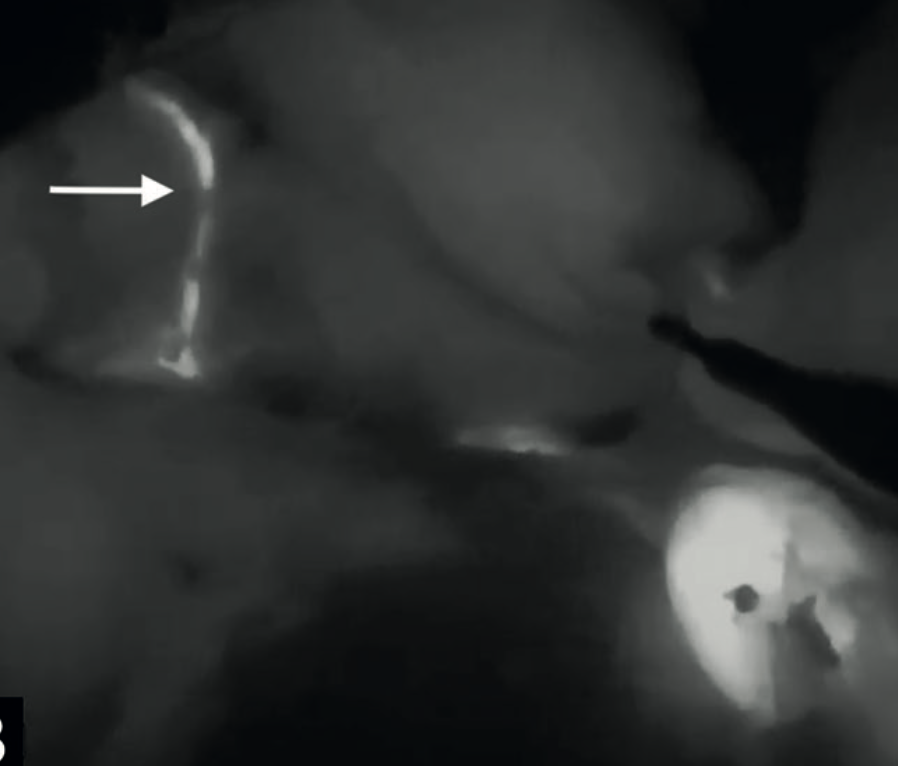

Los conductos de Luschka, son pequeñas estructuras biliares asociadas al lecho de la vesícula biliar. Originados principalmente de los conductos biliares del lóbulo derecho hepático, estos conductos presentan una gran variabilidad anatómica conun diámetro promedio de 2 mm.

Se presenta caso clinico guiado con verde de indocianina.